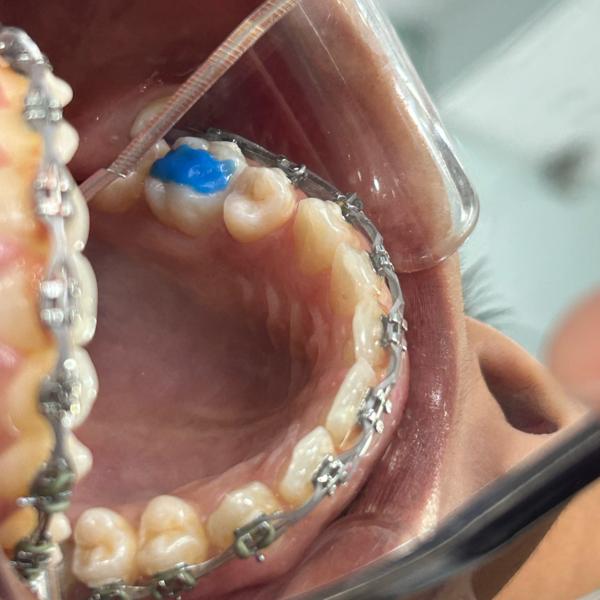

Image Gallery

Pictures That Speak